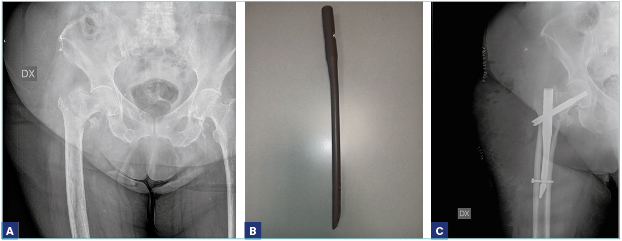

Per quanto riguarda la sede della frattura, la distinzione fondamentale deve essere posta fra le fratture mediali (intracapsulari) e le fratture laterali (extracapsulari). Nelle fratture mediali (sottocapitate, transcervicali) c’è un rischio elevato di necrosi della testa del femore e proprio per questo motivo, spesso, nelle fratture mediali, si è costretti a fare ricorso alla sostituzione protesica, mentre, nelle fratture laterali, è indicato il trattamento di osteosintesi (Figg. 1-5).

Anche l’età deve essere però un criterio di scelta del trattamento chirurgico. Nei pazienti più giovani (sotto i 60-65 anni) 7, è preferibile evitare l’intervento di protesi, in considerazione del fatto che si tratta nella norma di pazienti più attivi (che quindi sottoporrebbero l’impianto a degli stress maggiori) e che correrebbero il rischio, negli anni a seguire, di sottoporsi, vista la durata non indefinita di una protesi, a una revisione dell’impianto, intervento senza dubbio di maggiore complessità rispetto a un primo impianto. Si preferisce, per questo motivo, tentare di trattare i pazienti più giovani con un intervento di osteosintesi (viti cannulate, mini DHS) anche in caso di frattura mediale, sempre che la frattura sia riducibile 8. Le linee guida della SIOT, in accordo con le evidenze scientifiche maggiori, raccomandano l’osteosintesi anche negli anziani, in caso di fratture mediali composte. Questa scelta di trattamento ha dei pro e dei contro. I vantaggi sono la maggiore rapidità dell’intervento chirurgico, la minor perdita di sangue e l’accorciamento della degenza ospedaliera, tutti fattori che in un soggetto anziano possono essere determinanti nel ridurre le complicanze. Fra gli svantaggi, c’è sempre da considerare la possibile necrosi della testa del femore, che obbligherebbe il paziente a sottoporsi a un secondo intervento chirurgico di conversione della sintesi in protesi (il paziente deve essere adeguatamente informato su questo rischio). Inoltre, dobbiamo considerare la cautela che alcuni chirurghi pongono nelle disposizioni postoperatorie. Infatti, nonostante non ci sia concordia sotto questo aspetto, alcuni ortopedici preferiscono che il paziente operato di osteosintesi con viti eviti il carico per qualche settimana. Questo comporterebbe un rischio di allettamento, mai consigliabile in questa categoria di pazienti. È comunque assolutamente indicata una sintesi con tre viti (non con due) sui tre piani dello spazio, che conferisce maggiore stabilità.

Per quanto riguarda le fratture laterali (basicervicali, pertrocanteriche, sottotrocanteriche), l’indicazione condivisa universalmente è quella a un intervento di osteosintesi, che può essere effettuata con un chiodo-vite, rappresentato da un chiodo endomidollare che si introduce nel canale diafisario del femore e da una vite cefalica, con un angolazione variabile (si introduce nel collo del femore fino alla testa), o con una vite-placca, in cui la sintesi consiste in un sostegno laterale (la placca) più la vite cefalica, anche questa di varia angolazione. Nelle fratture sottotrocanteriche è raccomandato l’uso del chiodo endomidollare di lunghezza variabile in base alle caratteristiche e alla sede della frattura.